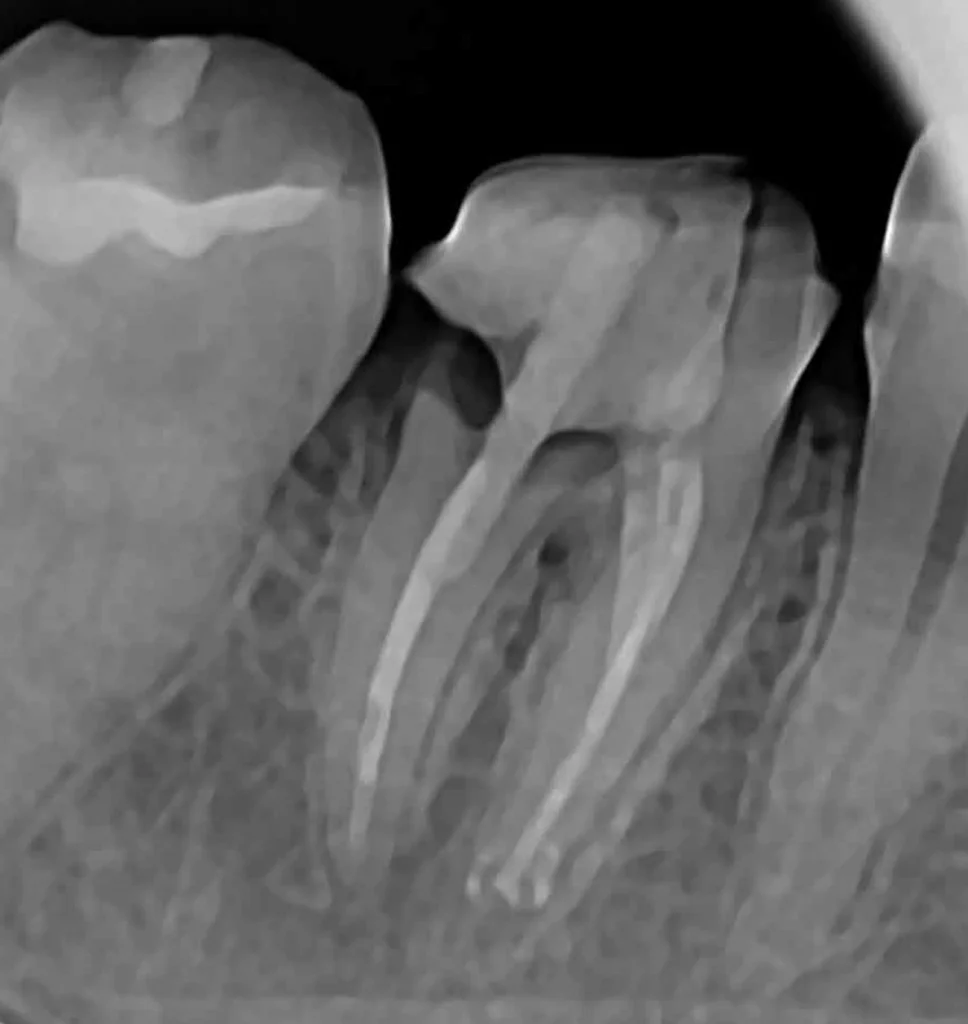

This woman had a badly broken down lower molar that had split apart and had been painfully abscessing for months. Unfortunately, it was beyond saving, and it was extracted. Keen to have the space restored, the patient opted to have an implant placed.

Below shows the crown fitted on to the implant post.